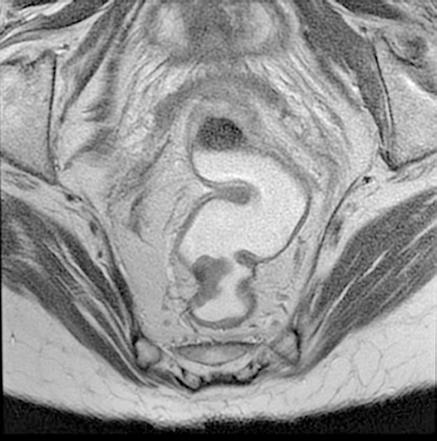

Figura 2 (A y B).

RM: Gran masa hepática localizada en segmentos VII, V y parte del IV. Comportamiento radiológico característico de hepatocarcinoma.

A) T1, imagen hipointensa entre VSH derecha y media.

B) T2, lesión hiperintensa con centro hipointenso.